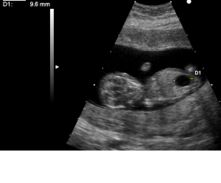

| Nuchal translucency/free beta/PAPPA screen | 10–13.5 | 91% | 5% | Uses ultrasound to measure Nuchal Translucency in addition to the freeBeta hCG and PAPPA ( pregnancy-associated plasma protein A). NIH has confirmed that this first trimester test is more accurate than second trimester screening methods. |